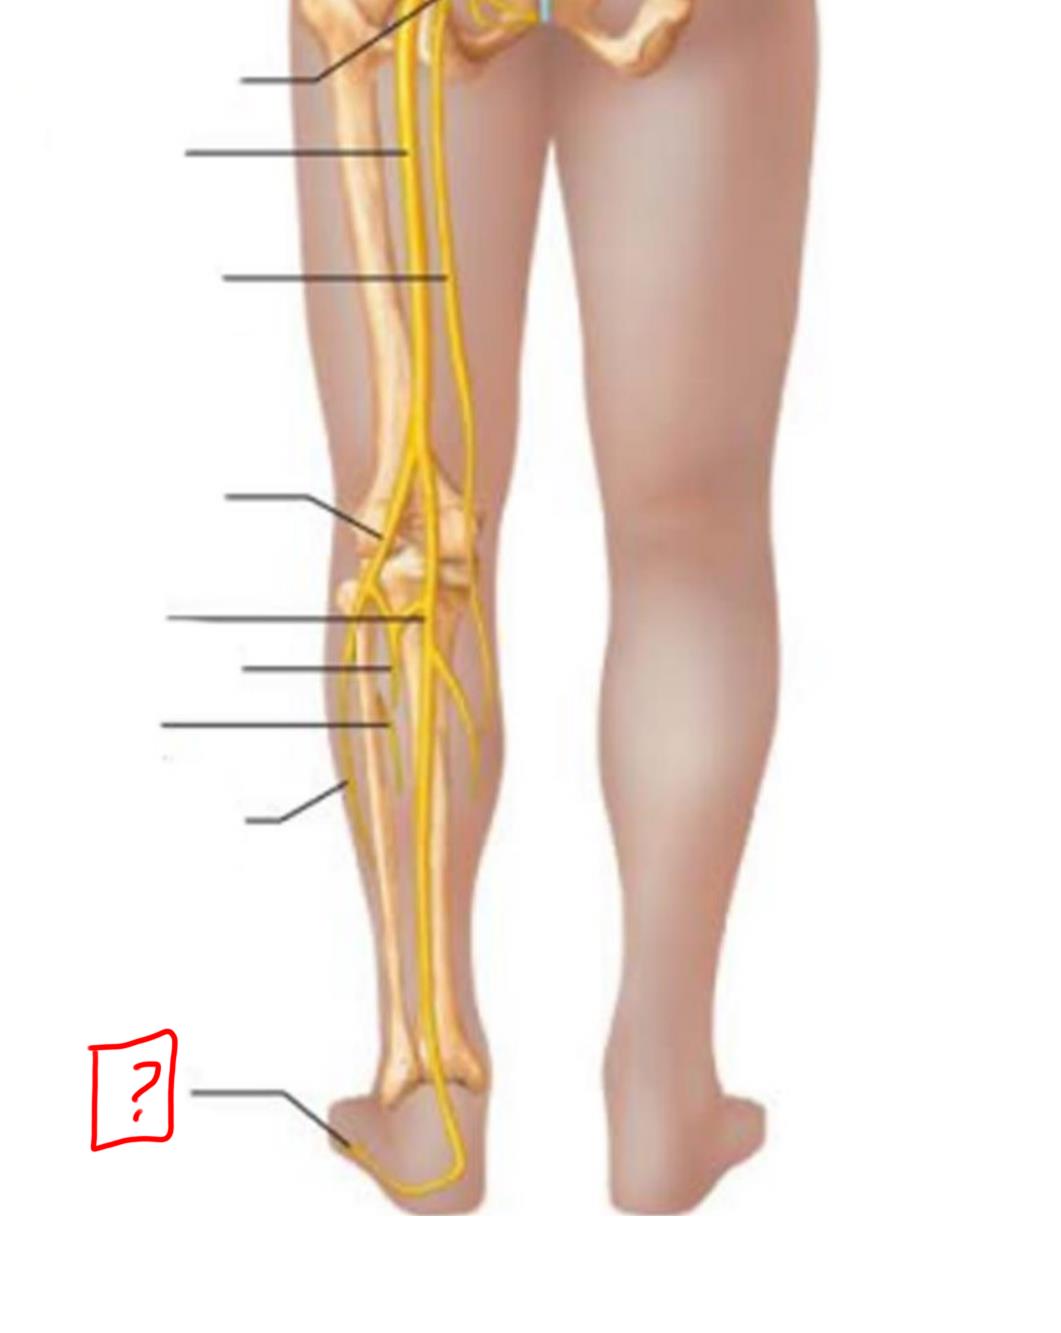

common fibular

tibial nerve

sural (cut)

deep fibular

superficial fibular

plantar branches